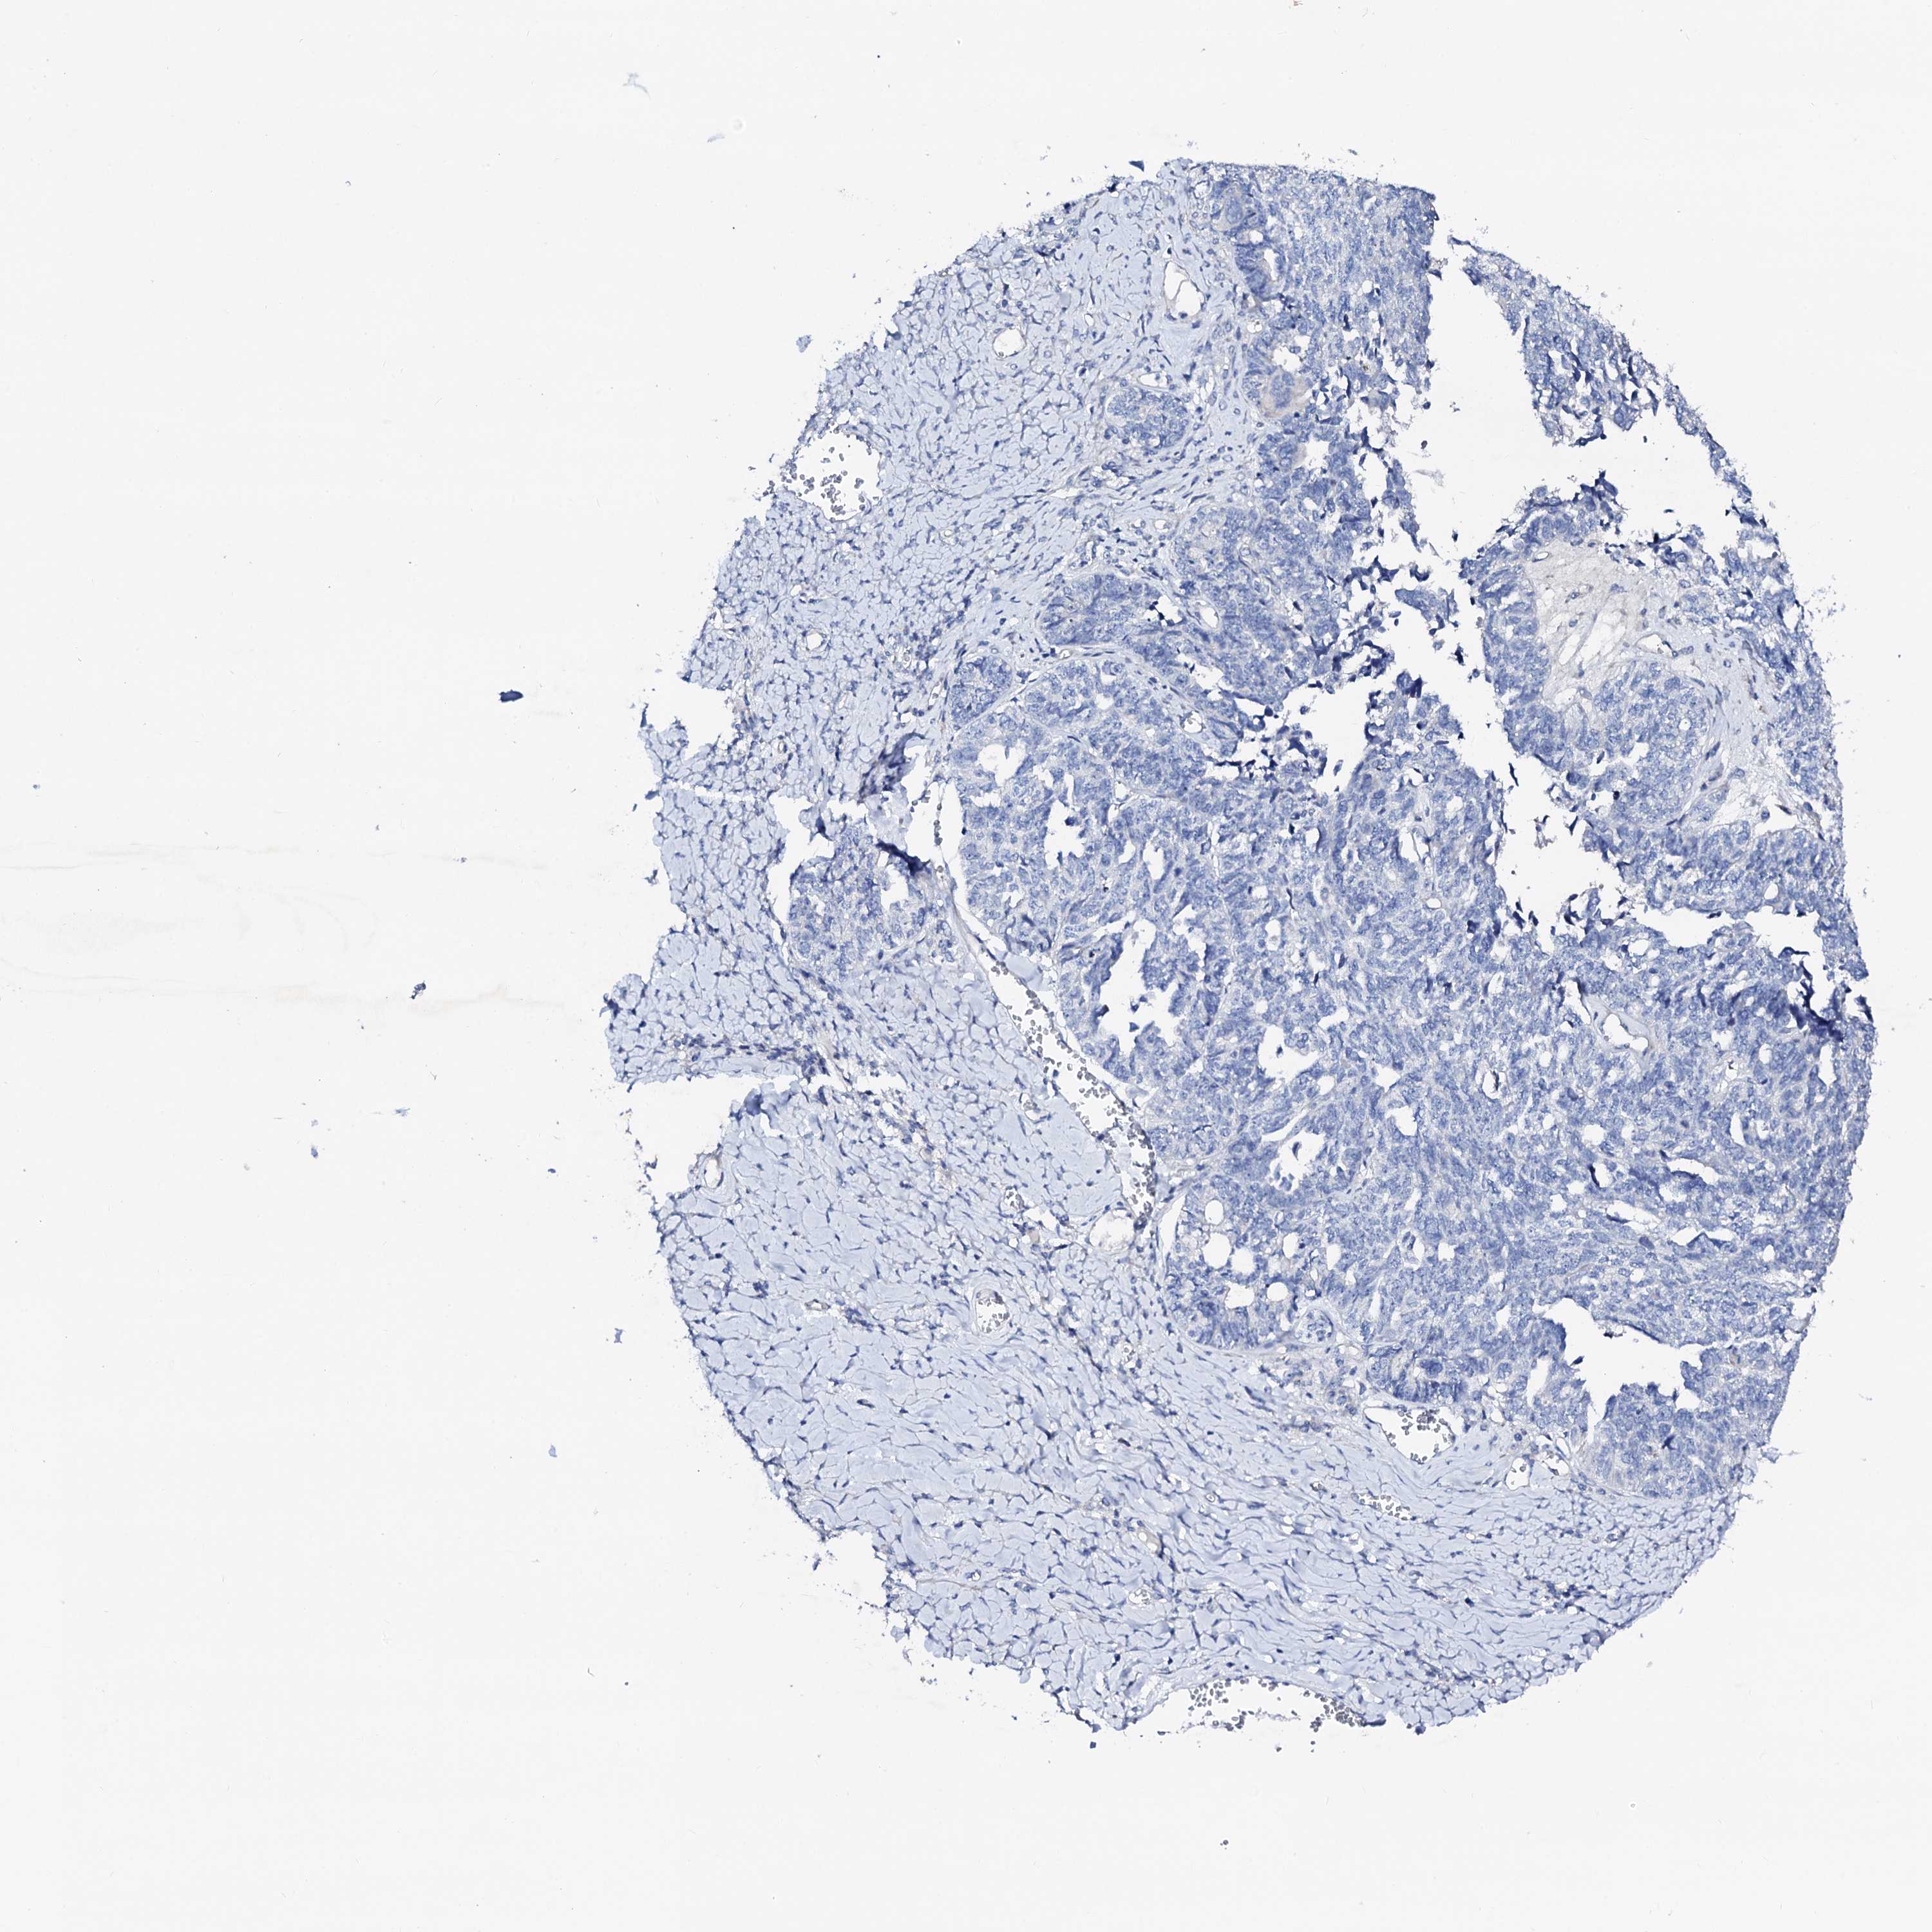

OVARIAN CANCER - Protein expressioni

A mouse-over function shows sample information and annotation data. Click on an image to view it in a full screen mode. Samples can be filtered based on level of antibody staining by selecting one or several of the following categories: high, medium, low and not detected. The assay and annotation is described here.

Note that samples used for immunohistochemistry by the Human Protein Atlas do not correspond to samples in the TCGA dataset.

Antibody stainingi

Antibody staining in the annotated cell types in the current human tissue is reported as not detected, low, medium, or high, based on conventional immunohistochemistry profiling in selected tissues. This score is based on the combination of the staining intensity and fraction of stained cells.

Each image is clickable and will lead to virtual microscopy that enables deeper exploration of all samples and also displays staining intensity scores, fraction scores and subcellular localization as well as patient and tissue information for each sample.

Antibody HPA038226

Antibody HPA058226

Cystadenocarcinoma, serous, NOS

Carcinoma, endometroid

Cystadenocarcinoma, mucinous, NOS

Carcinoma, NOS